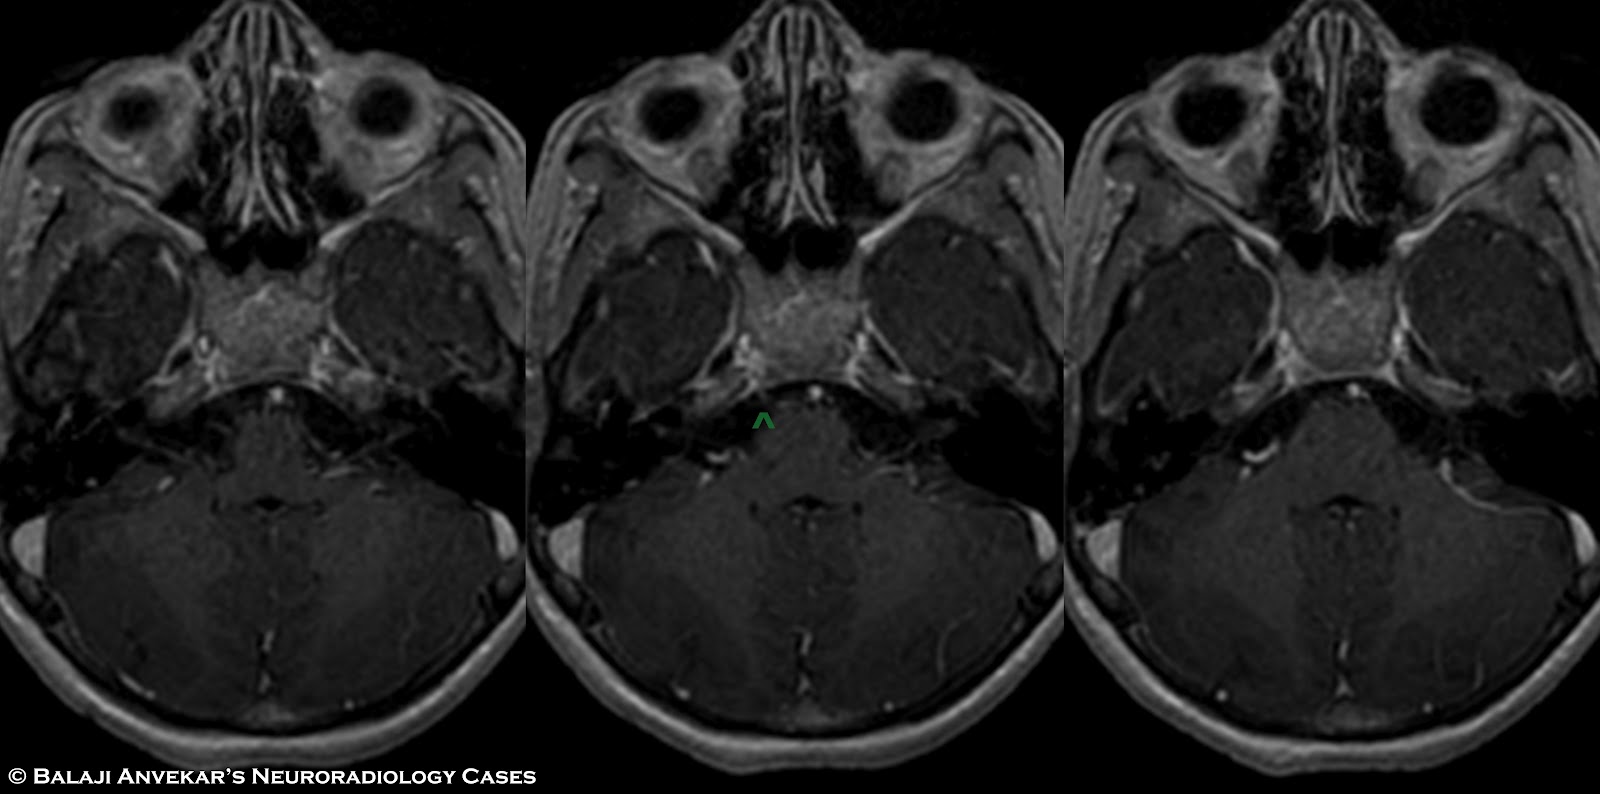

From left to right A) Axial FIESTA Sequence MRI brain of HGPPS What Is A Fiesta Mri It is used for visualizing cranial nerves at the skull base with high signal. The fiesta or truefisp sequence is an ultrafast pulse sequence with fully balanced gradients. The contrast of fiesta images is. What Is A Fiesta Mri.